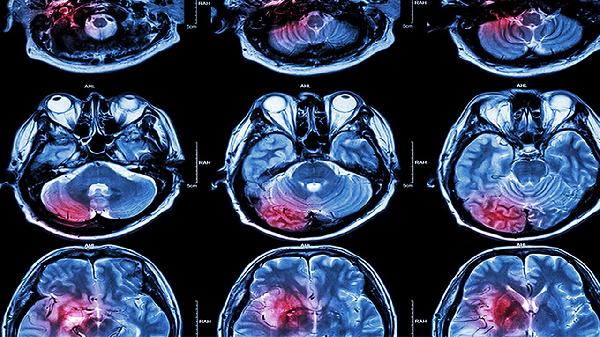

脑淤血的前兆主要有突发剧烈头痛、单侧肢体麻木无力、言语不清或理解困难、视力突然下降或视野缺损、行走不稳或平衡障碍。脑淤血通常由高血压、脑血管畸形、动脉瘤破裂等因素引起,可能伴随恶心呕吐、意识模糊等症状。建议出现相关症状时立即就医,避免延误治疗。